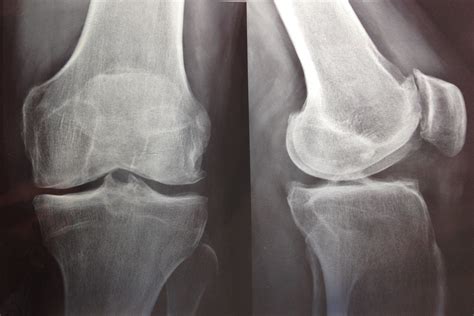

Diagnosing artritis en la rodilla involves a combination of medical history, physical examination, and diagnostic tests. The diagnostic process typically includes:

• Imaging Tests: X-rays, MRI, or CT scans may be used to visualize the knee joint and assess the extent of damage.

• Osteoarthritis: This is the most prevalent form of artritis en la rodilla, often referred to as "wear and tear" arthritis. It occurs when the cartilage that cushions the knee joint wears down over time, leading to bone-on-bone contact and inflammation.